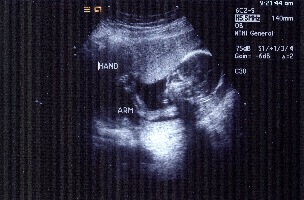

It's a Girl!